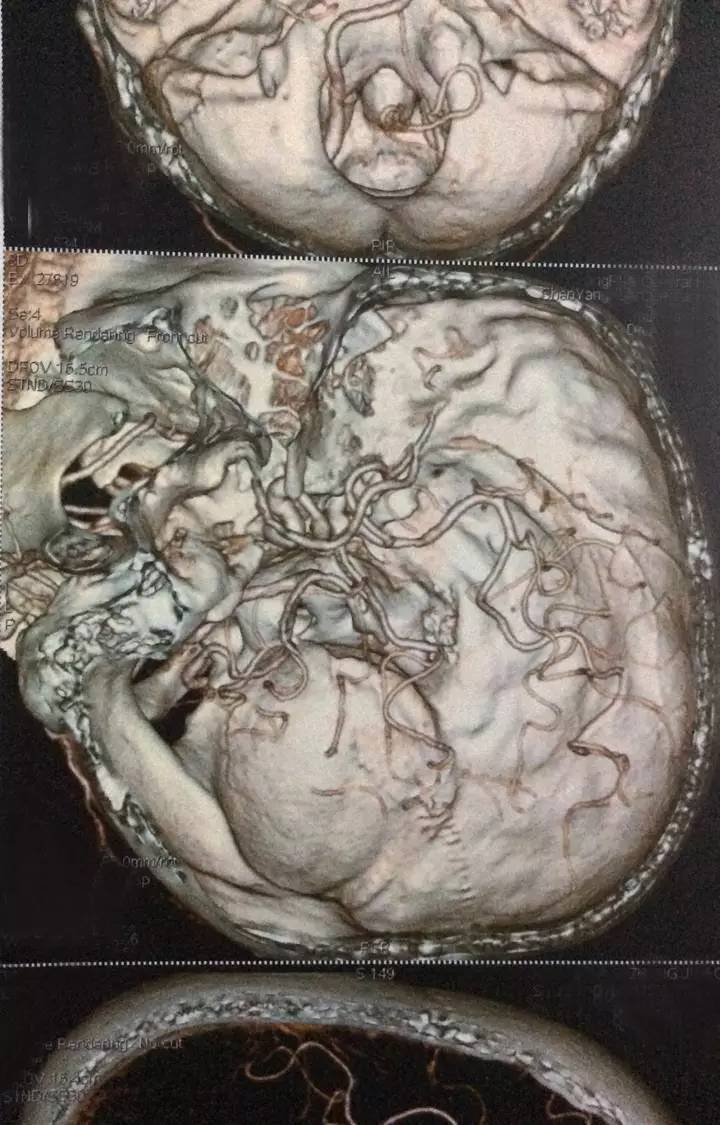

右侧椎动脉颅内段局限性显示纤细,余脑血管未见明显异常。

右颈内动脉近段混合斑块形成,管腔狭窄约20%;右椎动脉起始处非钙化斑块形成,管腔狭窄约40-50%,余颈部血管未见明显异常。

右侧椎动脉起始部存在中重度狭窄,但是需要血管造影检查更准确的判断其狭窄程度是否达到了重度。虽说左侧为优势椎,但是右椎有个优势的小脑后下动脉,因此提高了支架干预的倾向!此处支架的手术难度和风险不大,主要是术后一年内的支架再狭窄率较高(可高至20%左右)的问题需要特别强调。